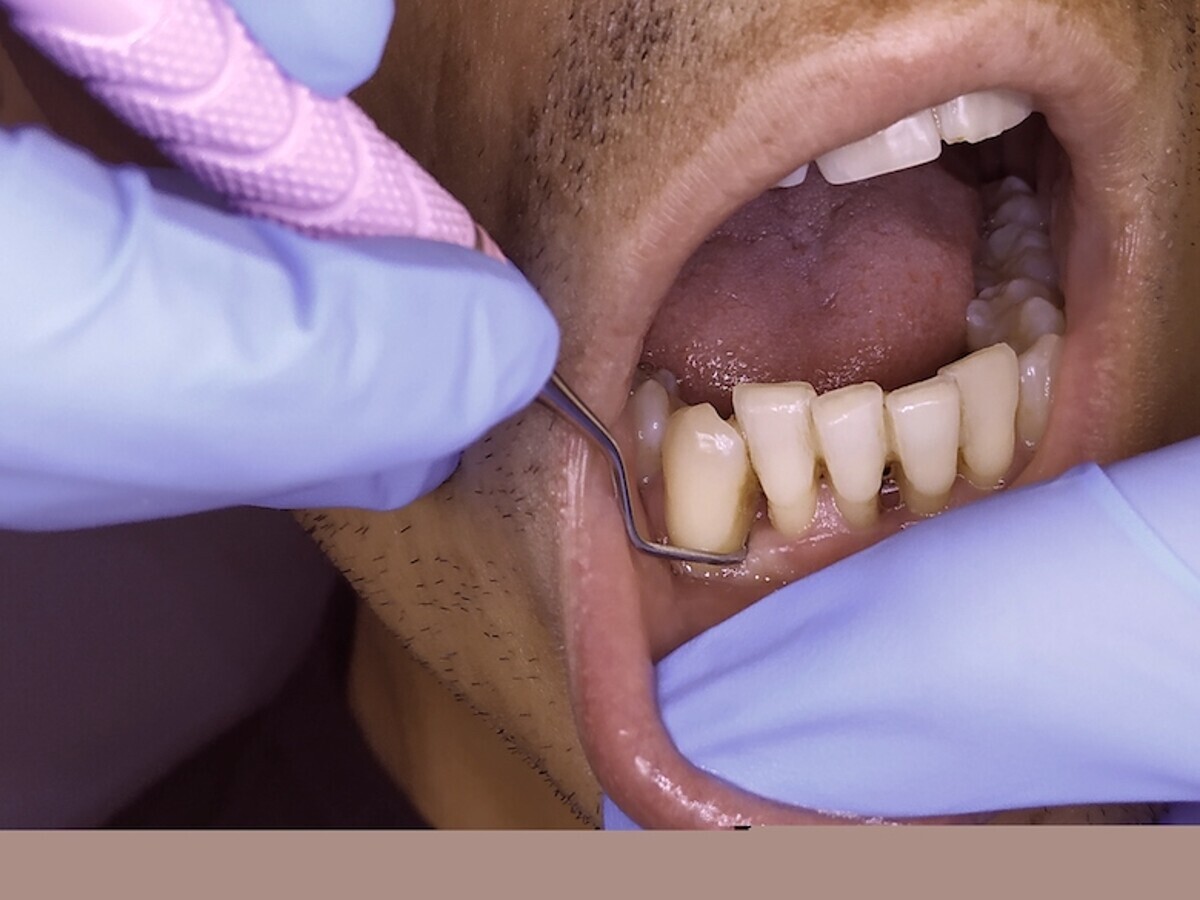

En la cirugía de tejidos blandos, la gingivectomía es probablemente uno de los tratamientos más básicos y que más frecuentemente se realizan en periodoncia quirúrgica (Figuras 17-19). Realizar una gingivectomía con láser es un procedimiento muy sencillo y a la vez bastante rápido que produce un efecto inmediato y que, comparado con una gingivectomía convencional con bisturí, ofrece una serie de ventajas como por ejemplo una hemostasia excelente, lo que mejora la visibilidad del campo y resulta en una molestia postoperatoria mínima para el paciente11.

La gingivectomía con láser es un procedimiento muy rápido y sencillo que ofrece beneficios comparado con una gingivectomía convencional (ver Figuras 17-19).

Fig. 17.

Fig. 18.

Fig. 19. Las figuras 17-19 muestran que la gingivectomía con láser es un procedimiento muy rápido y sencillo que produce un efecto inmediato y ofrece ventajas comparado con la gingivectomía convencional con bisturí.

Cuando el aumento del volumen de los tejidos blandos es grande y generalizado, estos agrandamientos gingivales son medicamentosos, y es en estos casos en los que la utilización del láser presenta ventajas realmente importantes y llamativas frente a la técnica convencional (Figuras 20 y 21).

Mavrogiannis y colaboradores publicaron un trabajo en el que compararon tres técnicas quirúrgicas diferentes para este tratamiento y concluyeron que la cirugía de colgajo no ofreció ventajas frente a la gingivectomía convencional respecto a recurrencia y que el índice de recurrencia fue significativamente menor en pacientes tratados con láser12.

Estas afirmaciones son verdades a medias en el sentido de que el láser, según esos mismos artículos reconocen, obtiene los mismos resultados que la técnica convencional, pero en mucho menos tiempo, con mayor comodidad para el dentista y máximo confort intra y post operatorio para el paciente, entre otras cosas.

Ahondemos pues en estas afirmaciones. Una de las cosas a tener en cuenta es que algunos tratamientos con láser, tanto quirúrgicos como no quirúrgicos, se hacen sin necesidad de usar anestesia local, lo que permite realizar tratamientos en toda la boca en la misma sesión, lo cual es bien aceptado por el paciente y requiere aproximadamente un 50% menos de tiempo que la técnica convencional13.

Además, el campo operatorio está prácticamente libre de sangre, en muchos casos no es necesario el uso de suturas y los pacientes refieren ausencia de dolor postoperatorio14. Otras ventajas son la precisión, la “esterilidad” del campo y la estabilidad y predictibilidad de los resultados de la interacción del láser con el tejido. La versatilidad del láser es patente en procedimientos como la cirugía plástica periodontal, el alargamiento coronario, la gingivectomía, la toma de muestras para biopsias, las segundas fases de implantes o las frenectomías de todo tipo15.